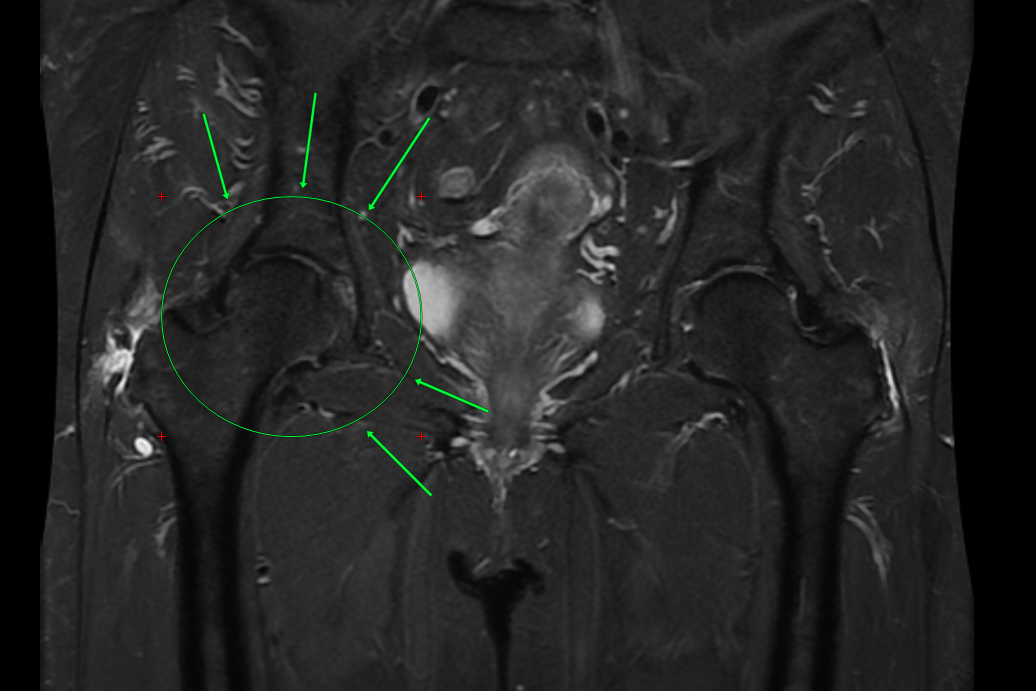

Я попросил показать МРТ. И увидел то, чего боялся увидеть: начальная стадия аваскулярного некроза головки бедренной кости.

Это когда кость начинает «умирать» из-за нарушения кровоснабжения. Если ничего не делать - прямая дорога к эндопротезированию. К замене сустава.

Но я увидел на снимке начальную стадию. Тот самый момент, когда процесс ещё можно приостановить. Когда движение - не враг, а единственный союзник.

Потому что на ранних стадиях некроза правильно подобранные упражнения улучшают кровоснабжение, снижают внутрикостное давление и реально тормозят разрушение.

• На МРТ есть положительная динамика - процесс остановился